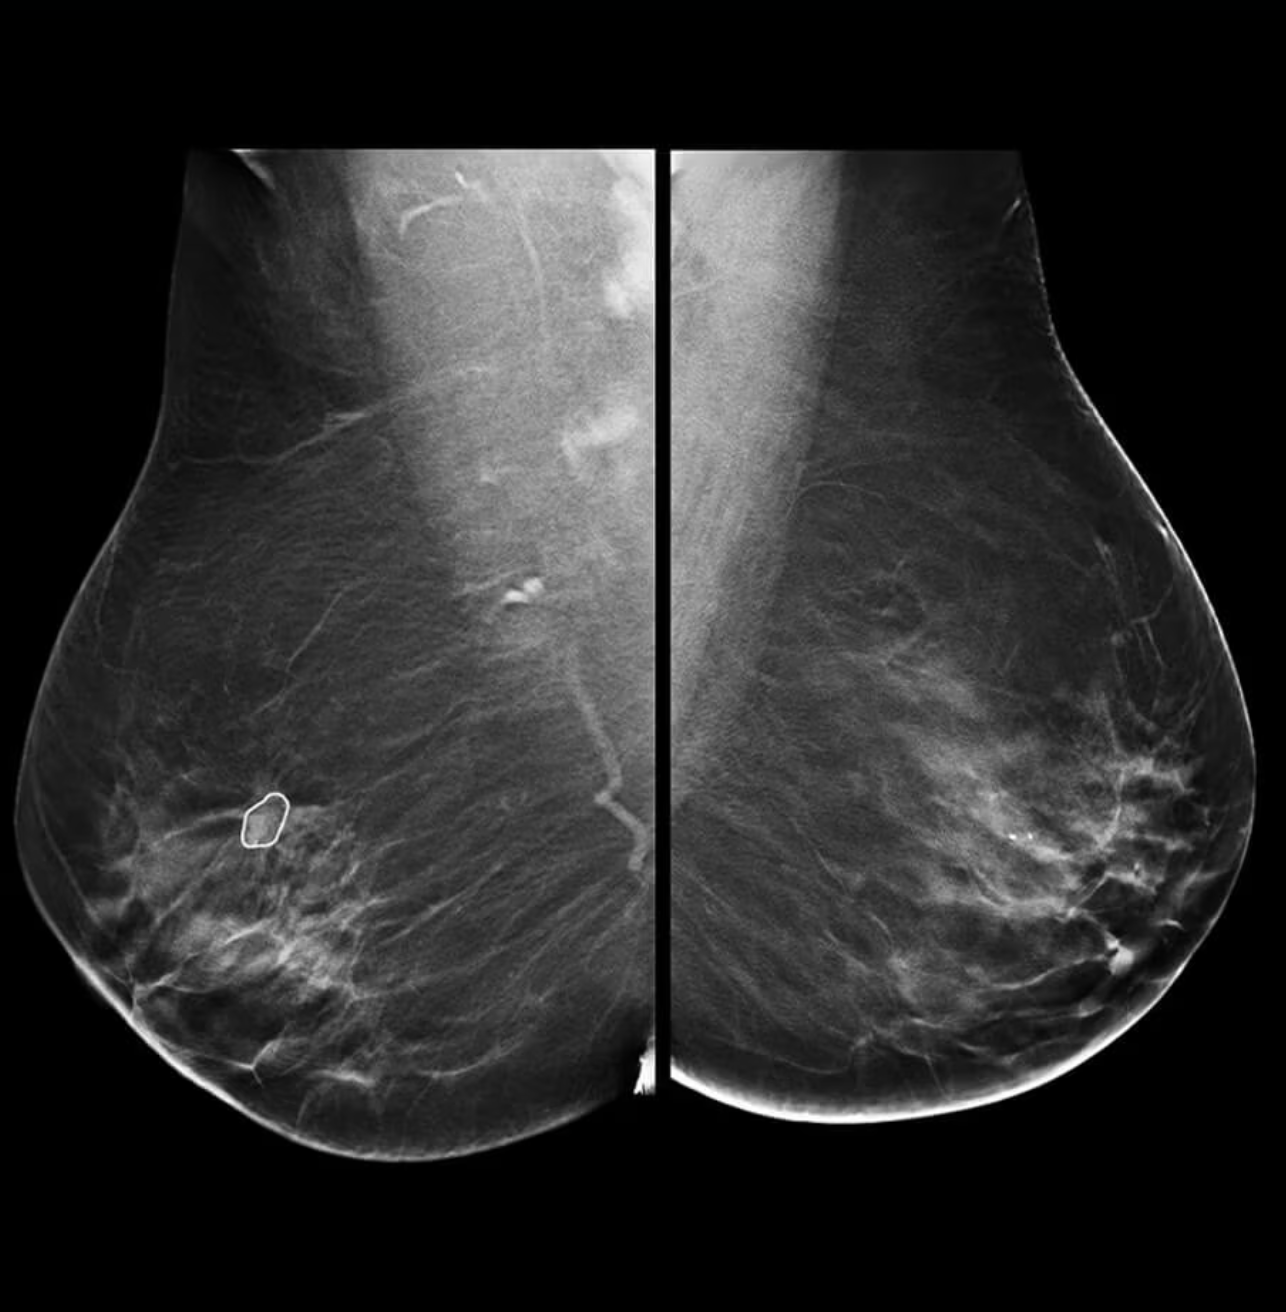

SEATTLE — Women who get their mammograms in the U.S. will now receive an additional layer of information from their...

Share on PinterestThe FDA will now require all mammography reports to include whether a person has breast density, which is...